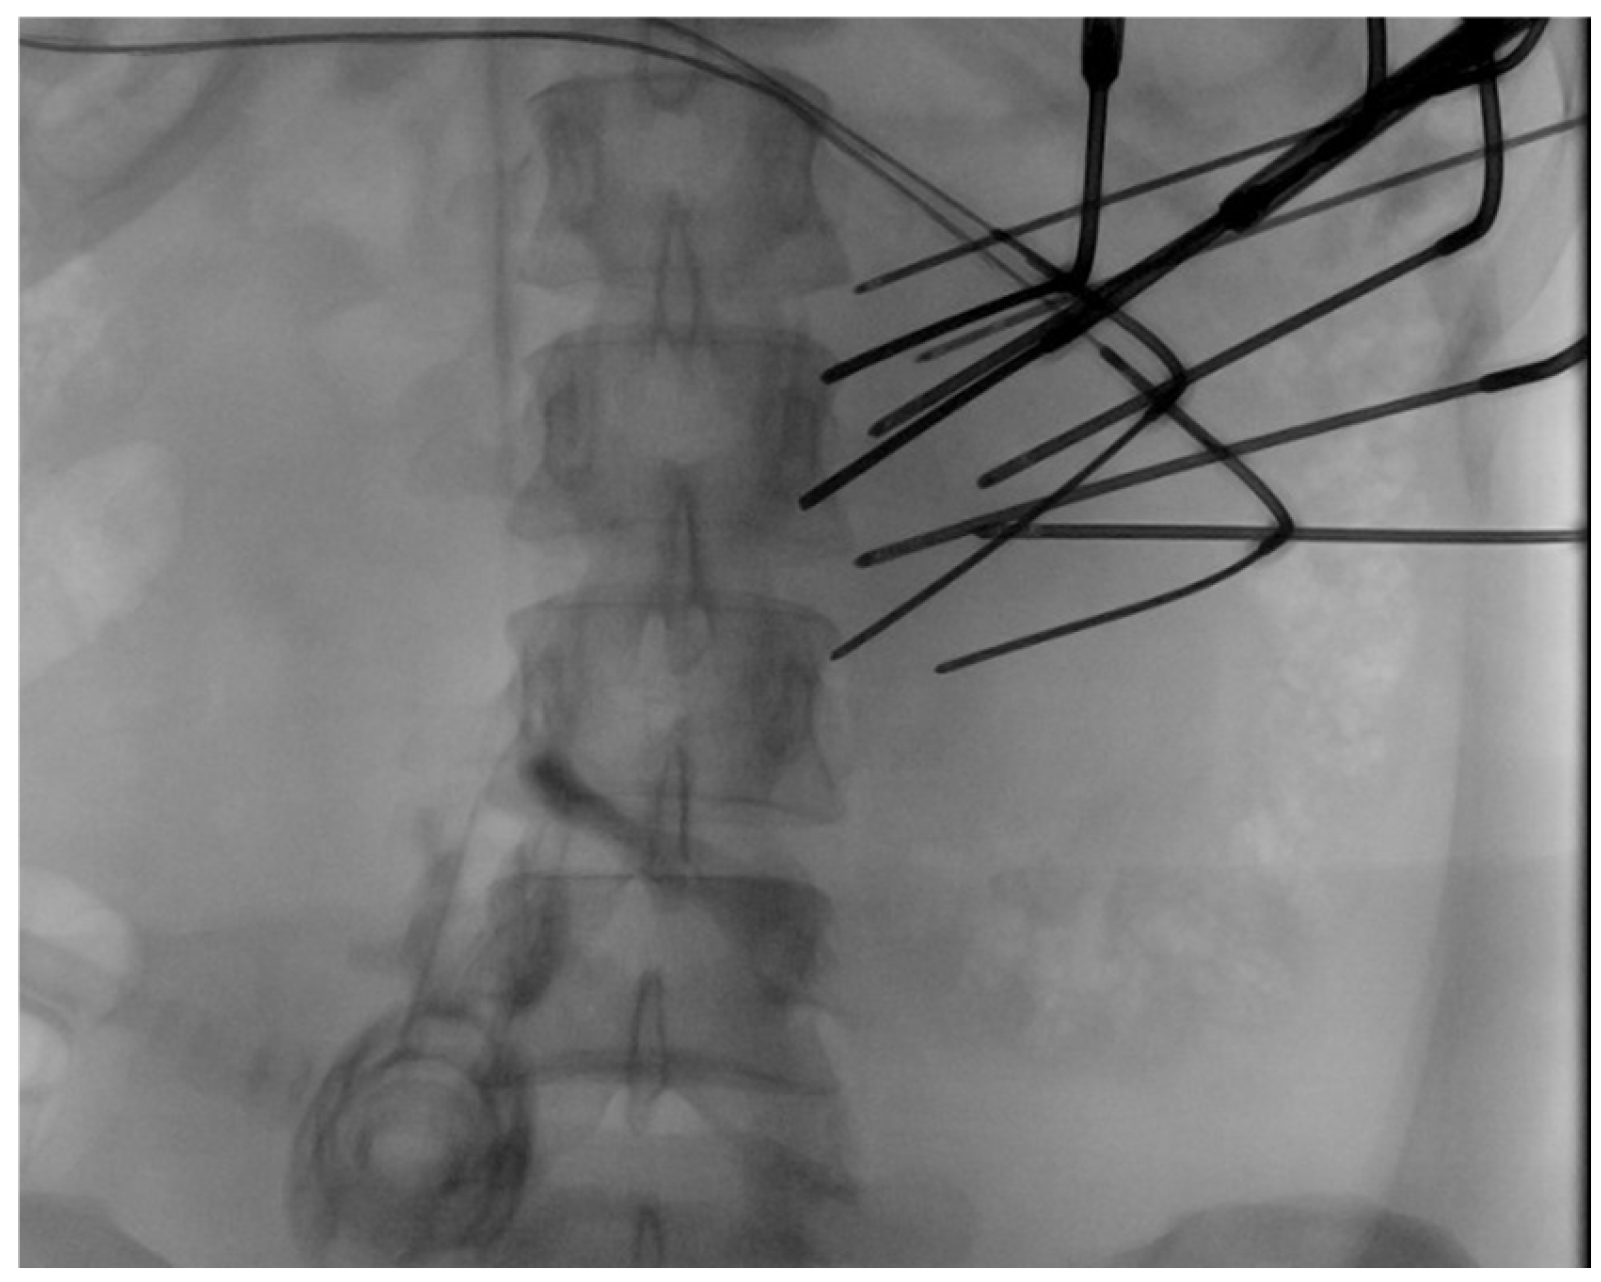

Cryoablation was conducted using a percutaneous, US, and CT-guided approach. Complete ablation was attempted in all cases, ensuring a 5–10 mm safety margin. Tumor puncture and probe advancement were performed under US guidance (Figure 2). Direct tumor puncture was achieved in all cases, and the CO2 did not interfere with US probe placement visualization. The probe placement was confirmed laparoscopically (Figure 3) and using mobile non-contrast CT. A variety of IceSphere and IceForce cryoablation probes (Boston Scientific, MA, USA) were selected based on the tumor size and the manufacturer’s predicted ablation volumes, as assessed by the interventional radiologist, with a spacing of 1–1.5 cm between probes. Hydro-dissection was performed between the tumor and skin to protect the skin, as well as application of sterile heat packs, while CO2 insufflation served as a barrier between the abdominal wall and intraperitoneal organs. Cryoablation was performed using a double-freeze protocol, consisting of two 10 min freezing cycles separated by a 5 min passive thaw. The first freezing cycle was performed using 100% freezing power, while the power in the second freezing cycle was adjusted to protect the skin. Ice ball formation and its extent were monitored laparoscopically (Figure 4), as well as by US and intermittent CT. Active thawing was initiated after the second freezing cycle to ensure resolution of the ice ball before the abdomen was desufflated, and ice spillage into the peritoneal cavity, if present, was suctioned using laparoscopic instruments. At the conclusion of the second freezing cycle, a final non-contrast CT scan was performed to delineate the maximum ablation zone, identify any untreated tumor areas, and confirm the absence of injury to adjacent structures. Following the procedure, the patients were transferred to the post-anesthesia care unit and admitted overnight for pain management and observation.

Figure 2.

Probe placement was performed image-guided, and the number of probes was determined based on intraoperative findings.

All three patients underwent ultrasound- and CT-guided laparoscopic-assisted percutaneous cryoablation (Figure 5). At diagnosis, the average tumor size was 5.4 cm (range 4.7–6.2 cm), increasing to 7.4 cm (range 7.1–7.6 cm) preoperatively. The mean tumor volume (TV) prior to cryoablation was 121.7 cm3. TV was estimated using the formula V = 0.5 × L × W × D, where V is the tumor volume, L is the tumor length, W is the tumor width, and D is the depth of the tumor [22]. All the patients initially underwent a period of active surveillance, which was unsuccessful because of tumor progression and worsening symptoms. The average procedure duration, including anesthesia, was 159 min (range 103–202 min), with a mean of 14 probes used (range 10–19). All patients were admitted for overnight observation and pain management following the procedure. Cryoablation was attempted with curative intent in all cases.

CT was used to confirm the placement of the probes prior to cryotherapy.